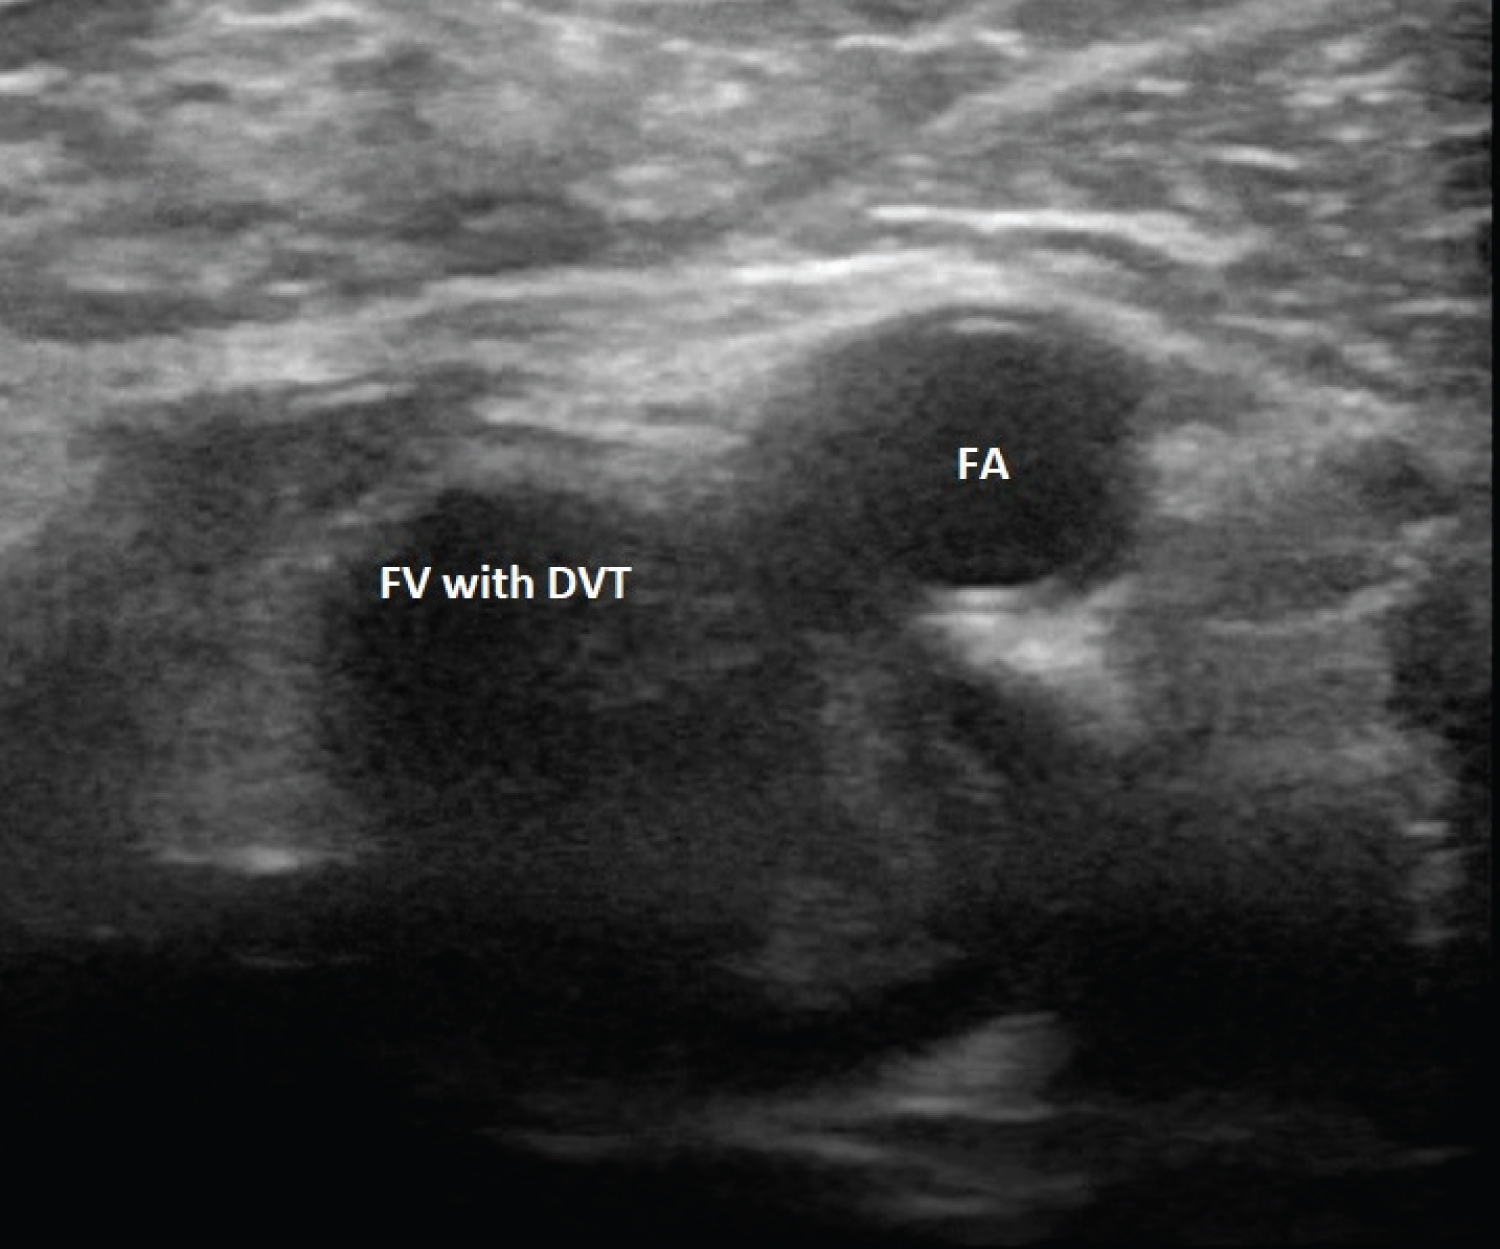

With the patient in the supine position, the examined leg slightly rotated externally, and with a gentle flexion of the knee, ECUS was performed by compressing the deep veins, starting with the common femoral vein (Figure 1), and compressing for every centimeter, continuing just proximal to the division of the popliteal vein (Figure 2). The linear transducer (3-12 MHZ linear transducer, GE Venue) was used for the examination and was placed transversely, perpendicular throughout the examination [12].

Figure 2: Ultrasound image showing the left femoral vein (FV) containing thrombosis and the femoral artery (FA). View Figure 2